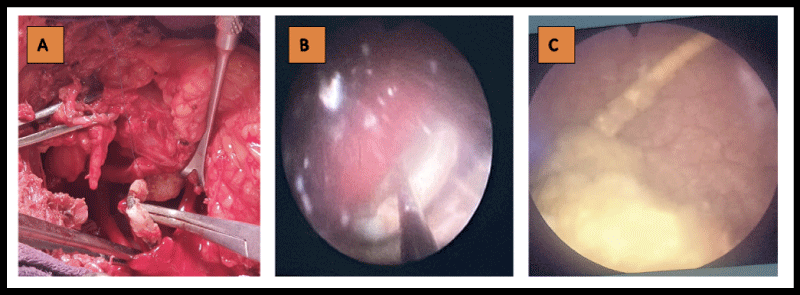

The main indication for JJ stent was lithiasis, as shown in (Table 1). JJ stent was unilateral in 33 patients (14 on the right and 19 on the left) and bilateral in 6. The mean duration of JJ stent use was 11 months (range: 4 months to 5 years).  Complications were either infectious or mechanical. Infectious complications were the main reason for hospitalization. Infectious complications were dominated by multidrug-resistant urinary tract infections, and mechanical complications by calcifications of the double J stent. Figure 1 and Figure 2 show an iconography of complications and intraoperative images.

Figure 1: A: Scan image of a calcified JJ lead; B: Scan image of a ruptured JJ lead; C: Scan image of a ruptured JJ lead + calcification of the lower loop. View Figure 1